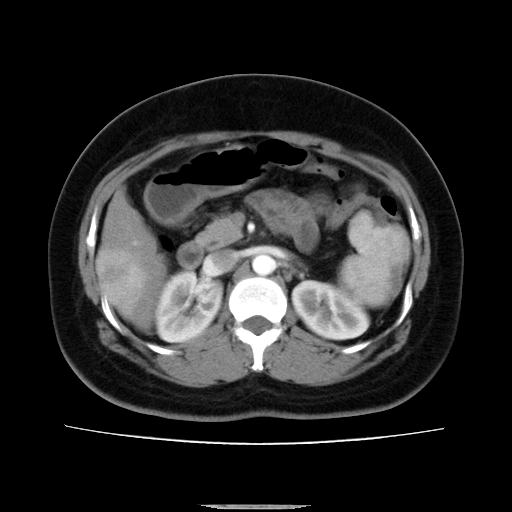

标题: CT14225:女性46岁。当地B超示肝内占位,来我院作CT检查。请 [打印本页]

标题: CT14225:女性46岁。当地B超示肝内占位,来我院作CT检查。请

肝内结节强化特点符合原发性肝癌表现,脾脏改变考虑为增大及先天发育所致。

动脉期病原灶明显强化高于肝密度且中央有无强化区,静脉期强化程度下降明显,延迟低于肝密度,考虑肝腺瘤可能性大,

符合肝癌表现,脾脏大(肝硬化?)

肝内结节强化特点:快进快出符合原发性肝癌表现

此患者虽然符合快进的特点,却不符合快出的特点,因为门脉期几乎是等密度,不符合肝癌的增强表现,所以我考虑肝局灶性结节增生可能性大

肝内结节强化特点符合原发性肝癌表现。脾大。

快进快出,符合肝癌表现。脾脏改变考虑为增大及先天发育所致。